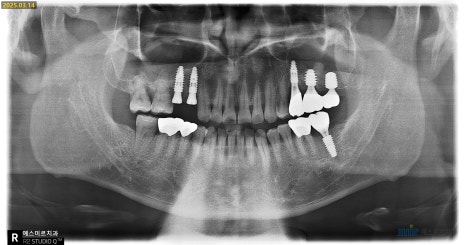

📍 내원 당시 상태

환자분은 왼쪽 위아래 치아가 흔들리고,

잇몸이 붓고 통증이 심하다며 내원하셨습니다

파노라마, 3D CT 정밀 촬영을 통해

검사를 진행해보니

👉 왼쪽 위쪽 상악동(코 옆 공기주머니)에

염증이 가득 차 있고,

뼈도 많이 녹아 있는 상태였습니다

🦷 발치 & 뼈이식& 임플란트 진단

상태가 심각해 왼쪽 위 #25,26 치아는 발치가 필요했고,

임플란트를 심기엔

뼈가 거의 없는 상태였습니다

특히

볼 쪽 뼈(협측골)은 염증으로 많이 녹아 있었고,

상악동(위쪽 뼈) 역시 염증으로

천공(구멍 발생) 되어 있는 상태였습니다